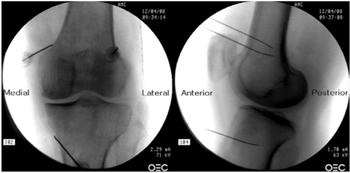

Radiofrecuencia de los nervios geniculados guiados por fluoroscopia

Para realizar una RFTNG guiados por fluoroscopia necesitamos una visión anteroposterior (AP) y lateral de la rodilla (Figura 2). Primero ubicamos al paciente en posición supina con una almohada debajo de la fosa poplítea (para que esté más cómodo) (16). Después de realizar asepsia y antisepsia de la rodilla, procedemos a ubicar los NG (Tabla II). El NGSL se encuentra avanzando la aguja de RFT hacia la confluencia de la diáfisis femoral lateral con el cóndilo femoral lateral en una visión AP y en un punto medio del fémur en una visión lateral. El NGSM se localiza avanzando la aguja hacia la confluencia de la diáfisis femoral medial con el cóndilo femoral medial en una visión AP y en un punto medio del fémur en una visión lateral. Por último, el NGIM se localiza avanzando la aguja hacia la confluencia de la diáfisis tibial medial con el epicóndilo tibial en una visión AP y en un punto medio de la tibia en una visión lateral (16,17).

Fig. 2. Proyección AP y lateral donde se observan las dianas terapéuticas usando fluoroscopia. Imagen tomada del artículo de Choi y cols. (9). Reproducido con la autorización de Jin Woo Shin.

Tabla II. Localización de los nervios geniculados guiados por fluoroscopia

Es muy importante tener una buena visión AP y lateral. En la proyección AP, la articulación tibiofemoral debe tener una anchura similar a ambos lados de la rodilla con el interespacio abierto (9). En la proyección lateral, debe existir una correcta superposición de ambos cóndilos femorales para realizar un bloqueo satisfactorio de los NGSM y NGSL (18).